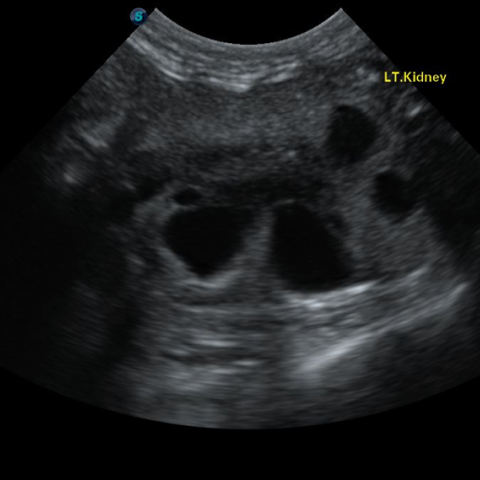

´Ù³¶¼º½ÅÀ庴

(PKD, Polycystic Kidney Disease)(Triaditis)

´Ù³¶¼º½ÅÀ庴À̶õ, ½ÅÀå¿¡ ´Ù¼öÀÇ ³¶Á¾ÀÌ ¹ß»ýÇϰí ÀÌ·Î ÀÎÇØ ½ÅÀå ±â´ÉÀÌ ÀúÇϵǸ鼭 ¼­¼­È÷ ¸¸¼º ½ÅºÎÀüÀ¸·Î ÁøÇàµÇ´Â ÁúȯÀÔ´Ï´Ù. ÁÖ·Î Æä¸£½Ã¾È, È÷¸»¶ó¾á °°Àº ´ÜµÎÁ¾ °í¾çÀ̵鿡°Ô¼­ ³ªÅ¸³ª´Â À¯Àüº´ÀÇ ÇϳªÀ̸ç, ´Ù³¶¼º½ÅÀåÀ» °¡Áø °í¾çÀ̵éÀº Æò±Õ 4¼¼¿¡ ÀÌ¹Ì ½ÅÀå ±â´ÉÀÌ ¼Õ»óµÇ±â ½ÃÀÛÇÑ´Ù°í º¸°íµÇ°í ÀÖ½À´Ï´Ù. µû¶ó¼­ ÀÌ·¯ÇÑ Á¾·ùÀÇ °í¾çÀ̵éÀÇ °æ¿ì ºñ±³Àû ¾î¸° ¿¬·ÉºÎÅÍ Áö¼ÓÀûÀ¸·Î ½ÅÀå ±â´ÉÀ» ¸ð´ÏÅ͸µ ÇÏ´Â °ÍÀÌ ÇÊ¿äÇÕ´Ï´Ù. ¶ÇÇÑ ½ÅÀå »Ó ¾Æ´Ï¶ó ÁÖº¯ Àå±âÀÎ ºñÀå, °£, ÃéÀå¿¡µµ ³¶Á¾ÀÌ »ý±â¸é¼­ À̵é Àå±âµµ ¹®Á¦°¡ µÉ ¼ö ÀÖÀ¸¹Ç·Î Á¤±âÀûÀÎ °Ç°­°ËÁøÀ» ÅëÇØ °í¾çÀÌÀÇ °Ç°­ »óŸ¦ È®ÀÎÇÏ´Â °ÍÀÌ ÁÁ½À´Ï´Ù.